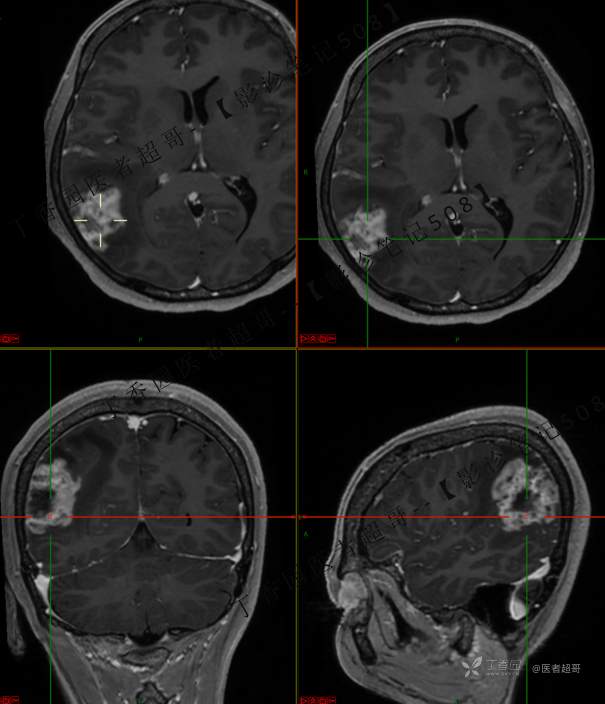

【影诊笔记508】同病异影,个人感觉有难度,欢迎分析,领丁当!有详细术程及病理!

患者性别:女

患者年龄:46岁

主 诉:突发一过性意识不清伴肢体抽搐5天余。

现病史:患者5天余前无明显原因及诱因出现一过性意识不清,伴肢体抽搐,持续约2-3分钟,后意识逐渐恢复,无明显头痛头晕,无恶心呕吐,无肢体抽搐,无呼吸困难,无二便失禁,后就诊于当地医院,行颅脑CT示“颅内占位性病变”,予以药物对症治疗,具体不详,门诊以“颅内占位性病变”,收入我科。患者自发病以来,未进饮食,近期体重无明显变化。